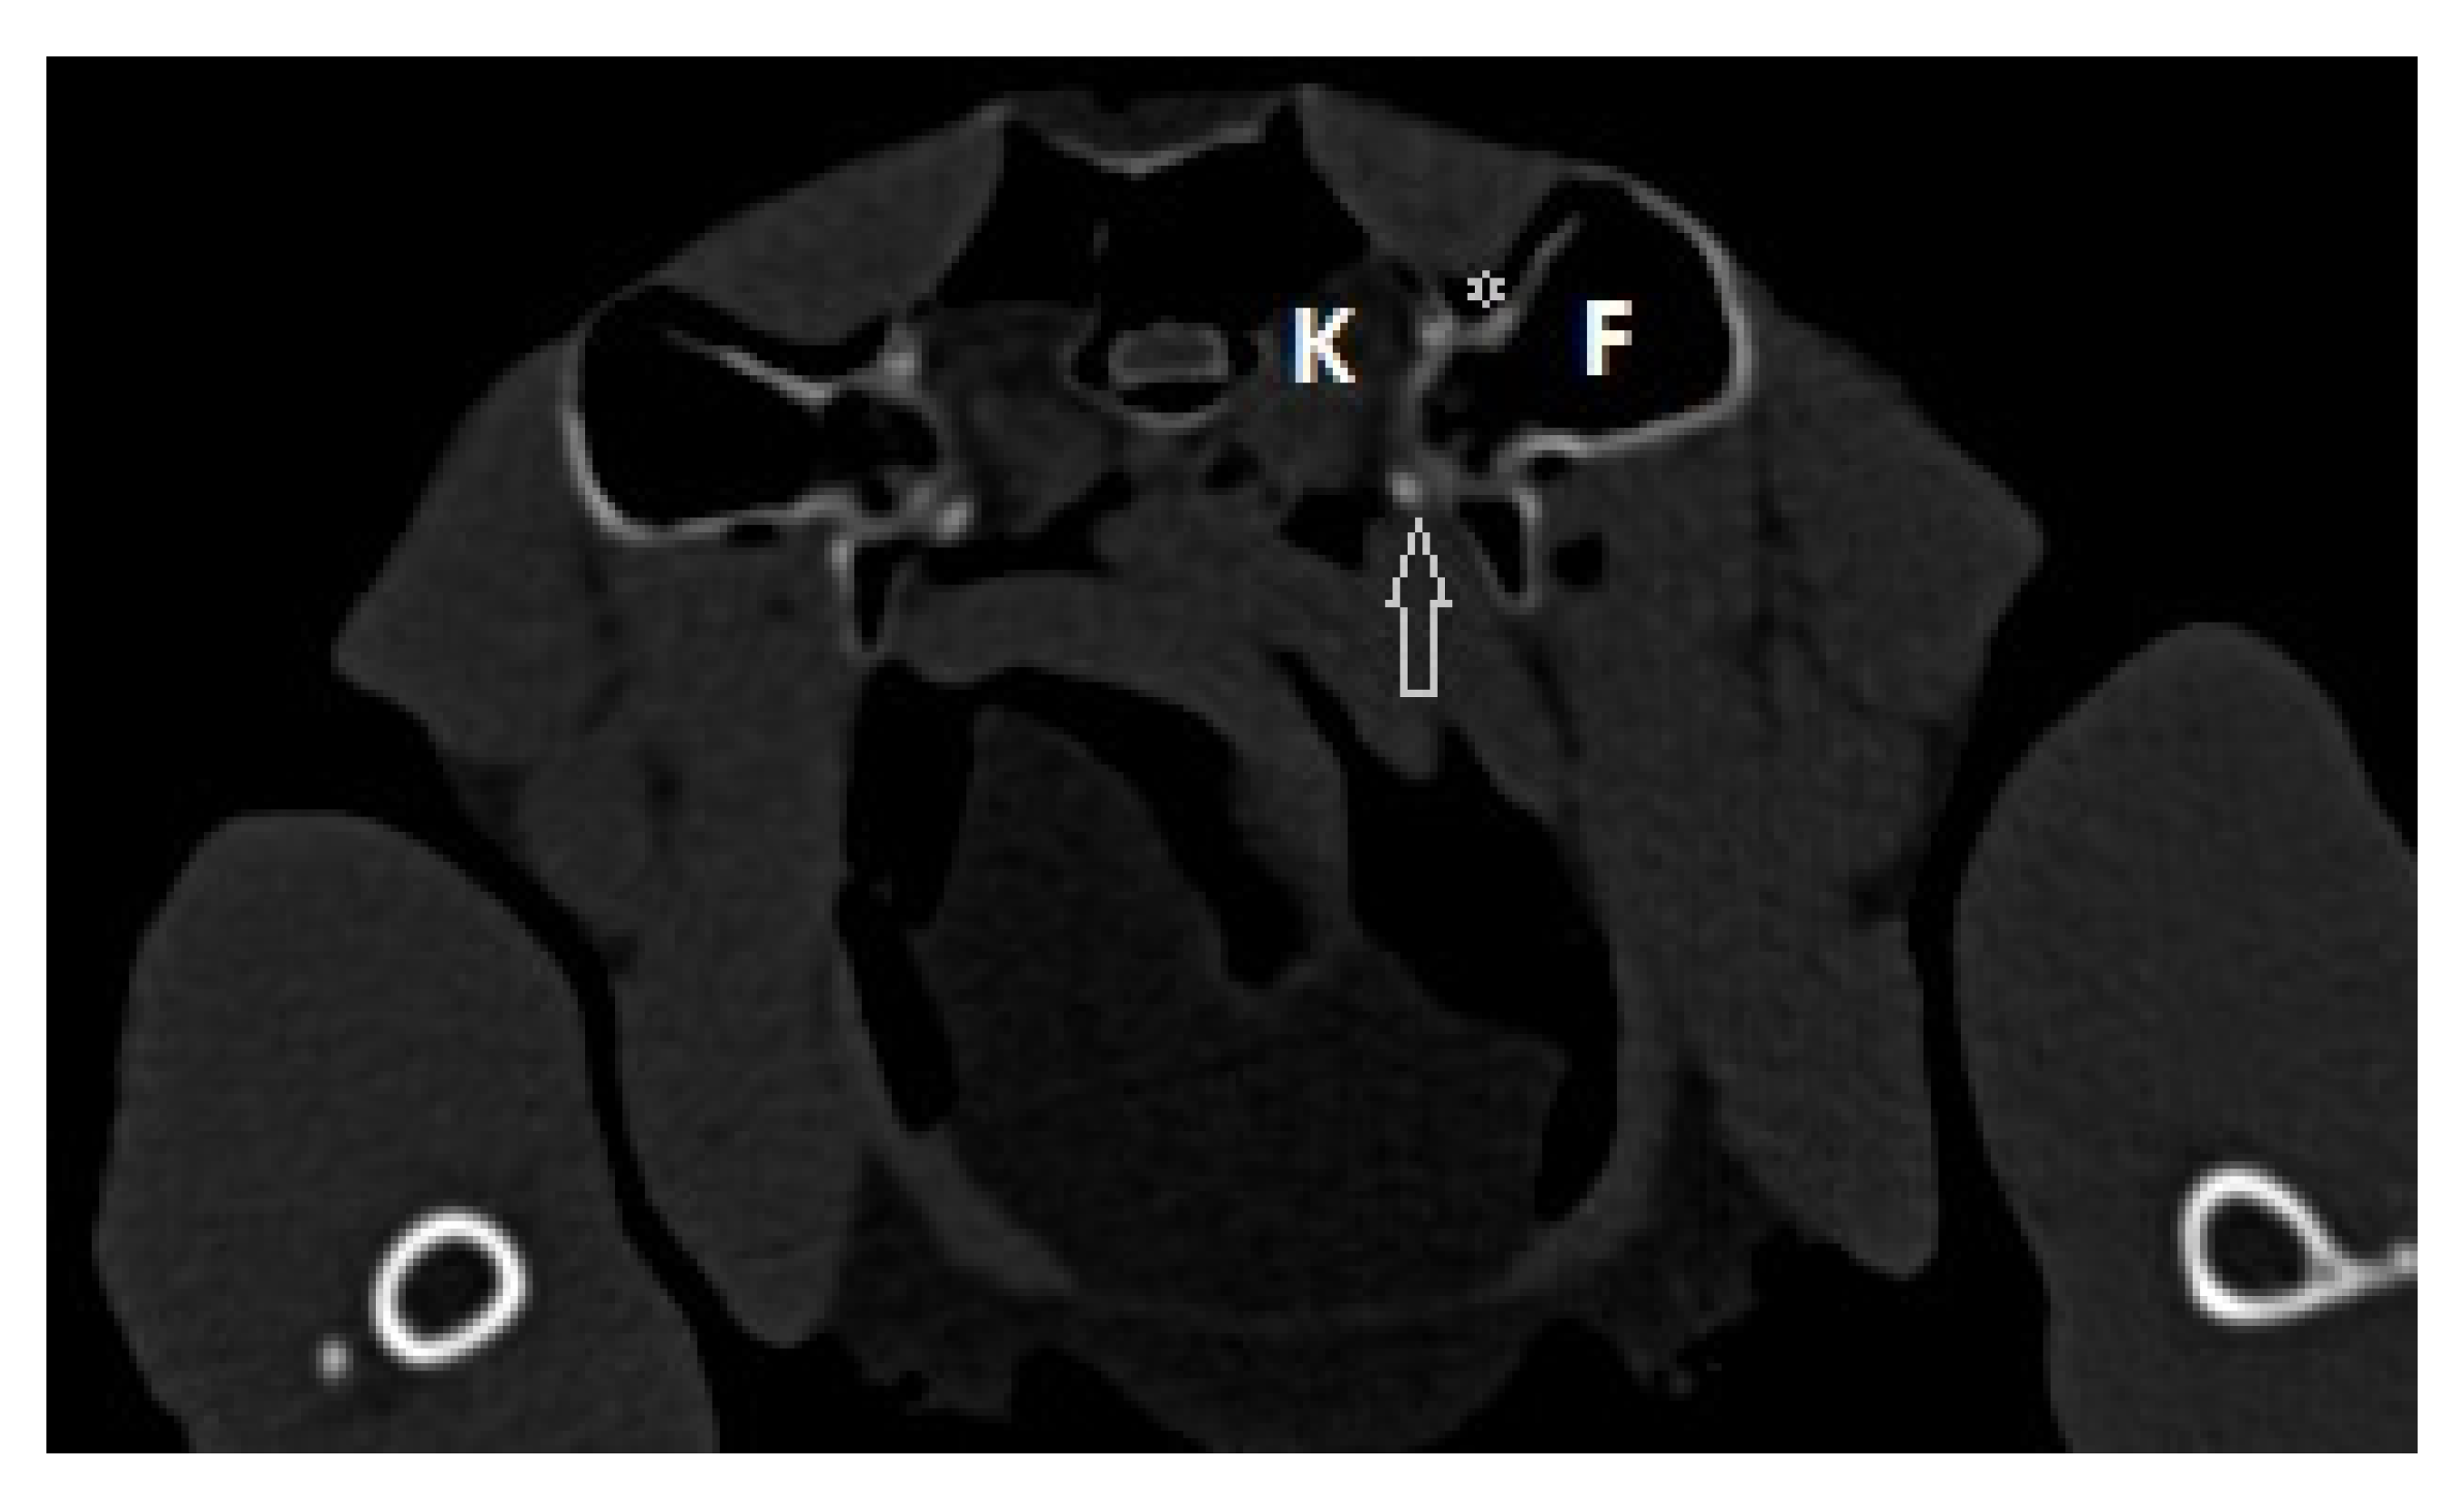

2.1. History and Clinical Examination

2.2. Surgical Procedure and Post-Surgery Management